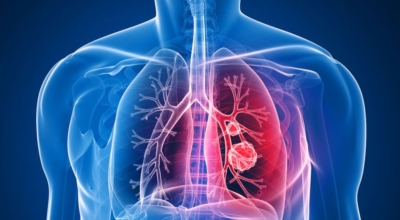

폐에 발생된 악성 종양을 말하며 오랜 기간 흡연해온 남성들에서 발병률이 높고 요즘 들어 가지가지 환경적인 요인의 영향과 간접흡연으로 흡연하지 않는 여성에서도 많이 발생하고 있어요. 증상을 느껴 병원을 찾았을 때는 수술하기 늦은 경우가 많아 사망하는 비율이 매우 높은 암입니다.

폐 자체에서 생기거나 다른 장기에서 발생된 암이 폐로 전이되어 나타나기도 하고 특별한 초기 증상이 없는 경우가 많다고 하며 암이 진행된 후에도 일반적인 감기 증상인 기침과 가래 외의 특이 증상이 나타나지않아 증상만으로는 진단이 쉽지 않아요. 폐암 역시 다른 암들과 마찬가지로 조기 발견 및 치료가 매우 중요하므로 일상 속에서 폐암 초기증상을 간과하지 않도록 주의를 기울여야 해요.